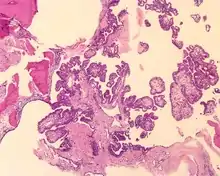

The microscopic appearance shows an unencapsulated, destructive growth, remodeling and invading bone. The tumor is arranged as simple, broad, non-complex papillary projections without large cystic spaces. The spaces are often fluid filled, have extravasated erythrocytes and/or inspissated material. The cells are cuboidal, usually single layered along the papillary structures, showing indistinct cell borders. The nuclei are round and hyperchromatic.[1][3][10][11]